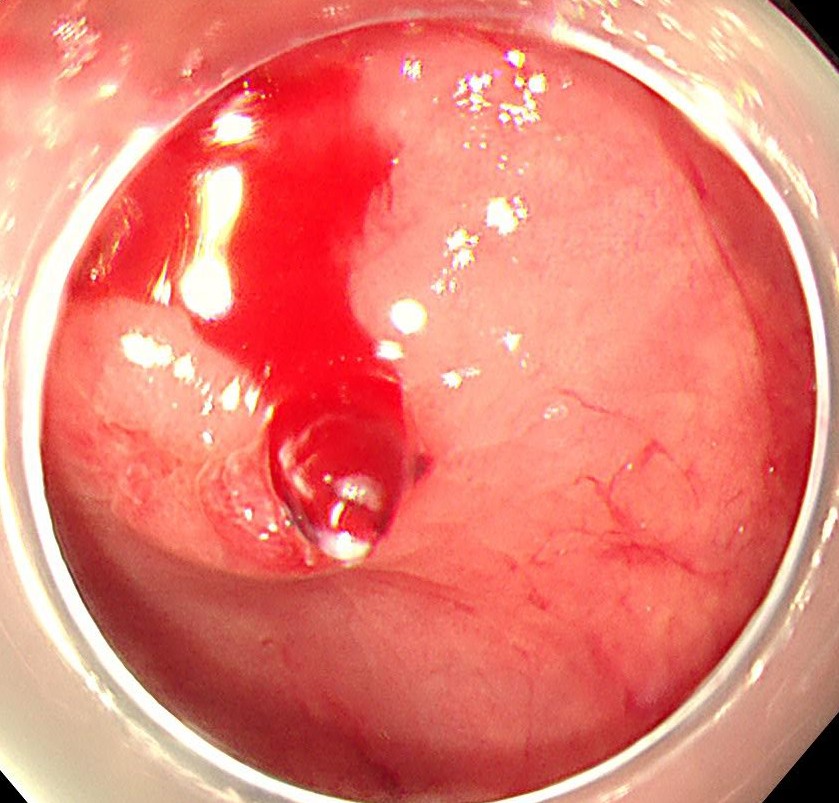

大量下血にて緊急大腸内視鏡施行、直腸Raに噴出性出血を伴う露出血管を認め、Dieulafoy潰瘍と診断しました。

まずはコアグラスパーを用いてソフト凝固60で止血します。